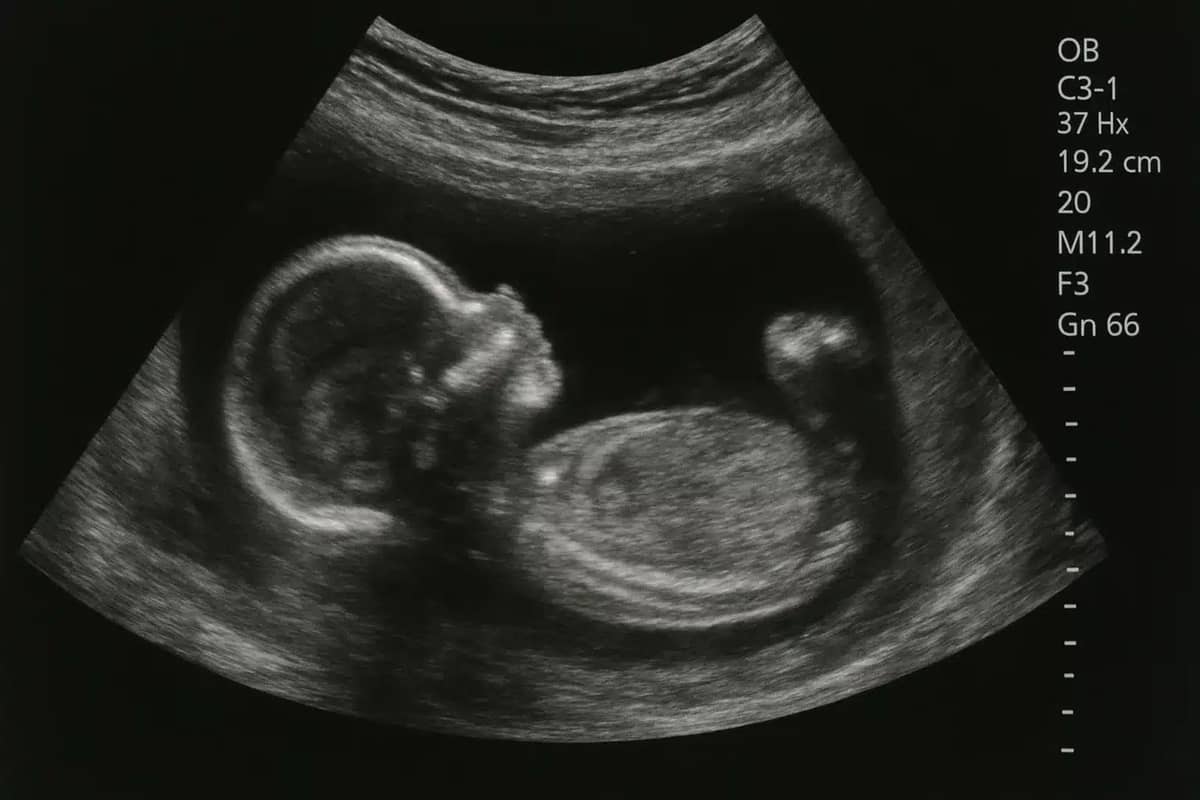

Founder Zhang Qifeng explained that the humanoid robot would be built with an artificial womb located in its abdomen.

Inside, artificial amniotic fluid and a nutrient hose would allow a fetus to develop in a way that mimics pregnancy.